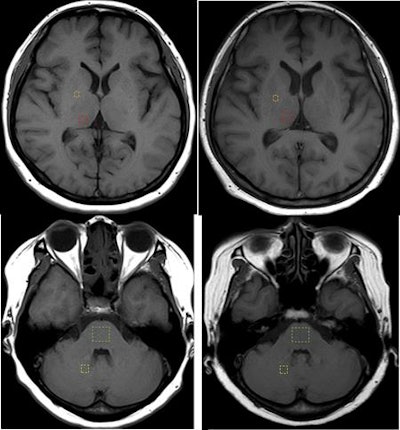

Regions of interest (ROIs) targeted the right dentate nucleus, central pons, right globus pallidus, and right thalamus. Two readers then compared the signal intensities of the four brain regions for the first unenhanced MRI scan and the last GBCA-enhanced scan. To determine any differences, signal-intensity ratios were calculated for the dentate nucleus and pons and for the globus pallidus and thalamus.